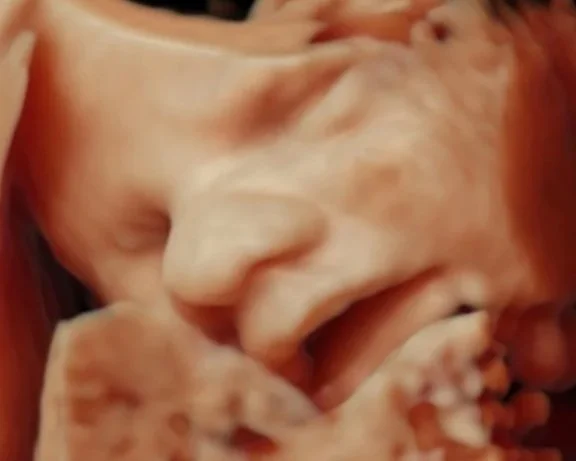

Seeing your baby suck their thumb, purse their little lips together, rub their eyes, and kick their little feet is magical.

During your session, you’ll watch your baby in real time—seeing their movements, their expressions, their unique rhythms. These are moments of life in utero that are usually unseen, yet deeply felt. Many families describe it as the first time everything becomes real in a new way.

• 2D & 3D are still images, while 4D/HD adds the dimension of motion, so it looks like a video. HD is the newest fetal keepsake ultrasound technology on the market. HD allows you to see all the details of the baby by using software technology to change the focal points and "lighting" of the ultrasound.